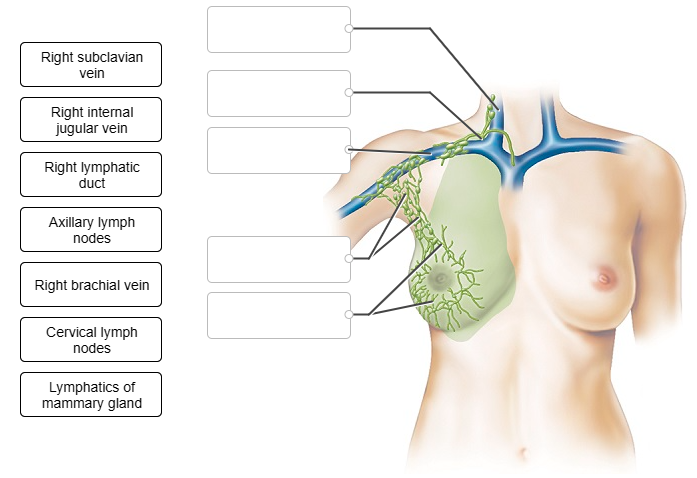

Label the figure showing the pathway for lymphatic drainage from the right breast.